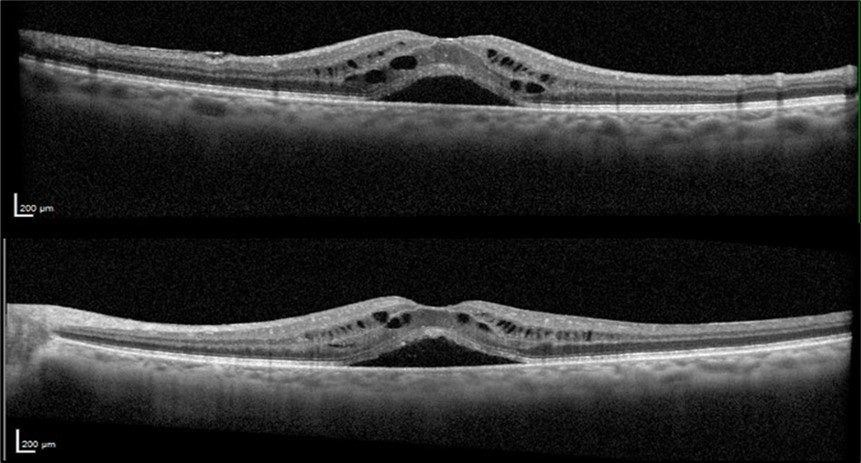

A 75-year-old female with underlying dyslipidemia and rheumatoid arthritis presented to the emergency department with a history of CME and reduced VA in both eyes (OU) for several months. She had undergone cataract surgery 20 years earlier in a different hospital and was currently using topical nepafenac, dorzolamide, and dexamethasone prescribed abroad. Initial VA in the right eye (OD) was 20/50 and in the left eye (OS) was 20/40. Fundus examination was notable for macular edema in OU. OCT OU revealed subretinal foveal fluid and intraretinal cysts (Figure 1).

Figure 1.Optical coherence tomography of both eyes revealing subretinal foveal fluid and intraretinal cysts at the patient's initial presentation to our clinic.